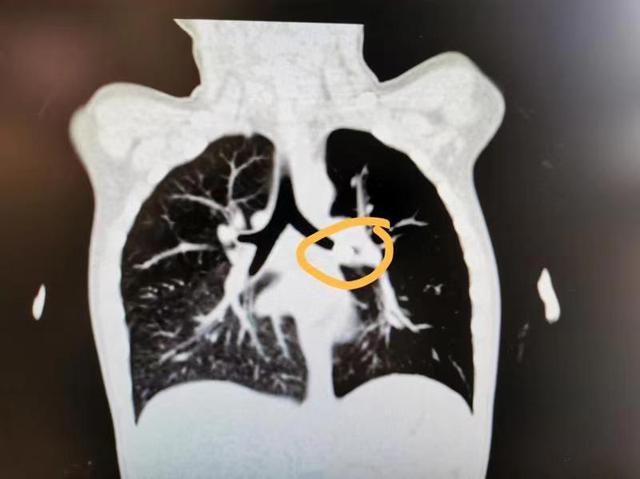

焦急的妈妈带着小外力直奔上海儿童医学中心 。 呼吸内镜团队第一时间安排了各项必要的术前评估 , 胸部增强CT提示:左主支气管远端存在12mm占位性病变 , 完全阻塞气道 , 由于病程较长 , 支气管壁粘膜可以看到增生的软组织和嵌合进软组织的金属阴影 。

呼吸内镜团队判断 , 这是一个典型的复杂性儿童气道异物案例 , 围术期和操作中稍有不慎 , 就可能会出现气瘘、大出血等严重并发症 。

经周全准备 , 手术开始了 , 医生们在术中发现 , 小外力左主支气管远端被一异物完全阻塞 , 上面覆盖了一层肉芽和炎性分泌物 。 清除肉芽和分泌物后 , 一个红褐色的异物显出原形——自带两个金属脚 , 稳稳地“驻扎”在左主支气管 。

呼吸内镜团队医生和麻醉、护理紧密配合 , 在异物暴露的三分钟内把这个“罪魁祸首”取出气道——原来是一个12mm*8mm的二极管 , 似乎来自某种玩具 。